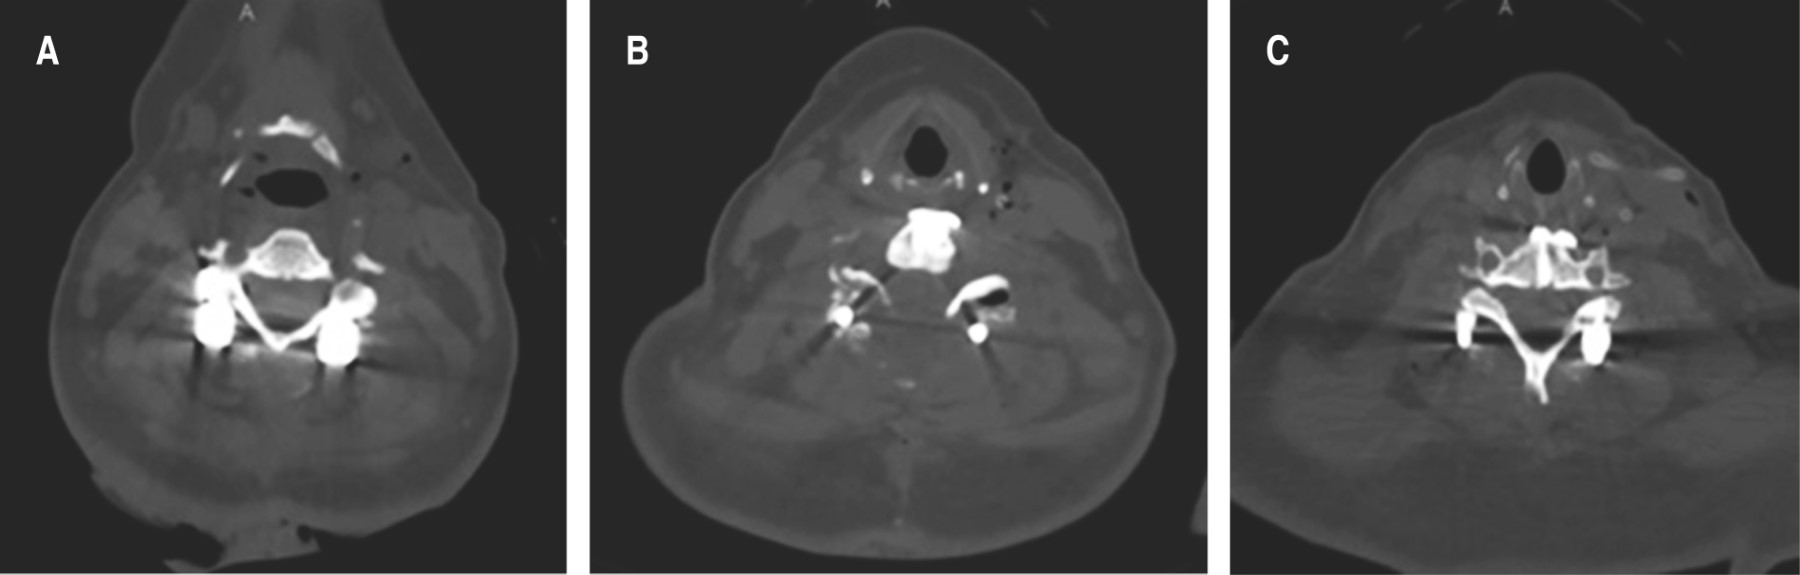

Paciente femenino de 66 años de edad, con diabetes mellitus tipo II, obesa e hipertensa de larga evolución; trasladada al sistema de urgencias de primer contacto tras sufrir accidente automovilístico tipo volcadura, ocupando el asiento trasero del copiloto sin cinturón de seguridad con pérdida de conocimiento referida por cinco minutos. Al momento del ingreso, durante la revisión primaria, se encuentra una paciente con escala de coma de Glasgow 12/15, sin compromiso de vía aérea, uso de collarín blando el cual es sustituido por collarín rígido, dolor en línea media cervical con sensación de escalonamiento, sin equimosis, extremidades superiores integras, con fuerza muscular C5-T1 3/5 bilateral, sensibilidad derecha C5-T1 1/2, izquierda C5-T1 2/2, ROTS hiporreflécticos, Hoffman negativo, reflejo pectoral de Bekhterev negativo, sin datos de inestabilidad clínica en pelvis, no se aprecian datos de bajo gasto cardiaco, extremidad inferior izquierda con fuerza muscular 3/5 de L2-S1, sensibilidad y ROTS presentes, extremidad inferior derecha con dolor, aumento de volumen ++ y crepito a la palpación en tercio proximal de pierna con pulsos distales presentes, tono de esfínter anal disminuido. Se realiza protocolo ATLS, se procede a solicitar valoración de neurocirugía con traumatismo craneoencefálico Marshall I y fractura luxación AO C6-C7:C (F4;N3;M1) evidenciada mediante tomografía axial computarizada clínicamente ASIA B (Figura 3); en revisión secundaria y con uso de estudios de imagen extendidos se reporta una fractura de meseta tibial derecha Schatzker VI AO 41C1.2, fractura diafisaria de peroné derecho AO 4F2b(a) y fracturas de arcos costales izquierdos 6, 7 y 8.

Se solicita resonancia magnética simple de columna vertebral cervical corte sagital y axial T2 con compresión medular a expensas de deslizamiento anterior al menos de 50% de cuerpo somático C6 sobre C7 con lesión de disco intervertebral C6-C7 y de complejo ligamentario posterior desde C6 hasta T1 SLICS 6 (Figura 3).

Ingresa para tratamiento quirúrgico con doble abordaje cervical en un solo tiempo quirúrgico. Se realiza un abordaje cervical posterior con estabilización a masas laterales C5-C7 e instrumentación transpedicular T2, laminectomía C6-C7, artrodesis posterolateral y, posteriormente, con la paciente en decúbito supino, se efectúa un abordaje cervical anterior con discectomía C6-C7 más fusión con caja intersomática PEEK C6-C7 y colocación de placa cervical anterior. La duración de la cirugía fue de cinco horas 45 minutos y un sangrado reportado de 600 mililitros (Figura 4).